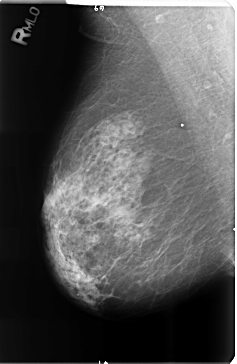

Volume: cancer_15 Case: B-3514-1

B_3514_1.RIGHT_MLO

RIGHT_CC LINES 4680 PIXELS_PER_LINE 3104 BITS_PER_PIXEL 12 RESOLUTION 50 NON_OVERLAY

RIGHT_MLO LINES 4720 PIXELS_PER_LINE 3072 BITS_PER_PIXEL 12 RESOLUTION 50 NON_OVERLAY